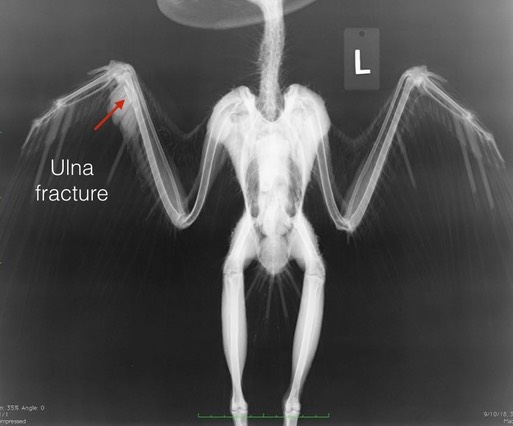

Western Screech Owl 18-675

Volunteer Bill picked up 18-675 one evening after he was found in the middle of a road on the Walla Walla University campus in College Place. He dropped him off at Animal Clinic East in Walla Walla the next morning so they could check the owl out before Bill brought him to Pendleton after work. They found no major new injuries, but healed fractures in the left ulna and right scapula. It is amazing what some birds can overcome. The owl had completely recovered from his injuries, was at a good weight, indicating he was hunting well. Hopefully we can get him out the door quickly, with instructions to avoid cars!